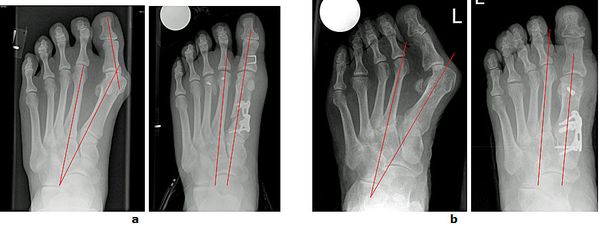

Abb.8: Korrektur des schmerzhaften Kleinzehenballen (Schneiderballen, Taylors bunion) durch die Kombination einer basisnahen Korrektur und einer Chevronette Osteotomie.

a Fehlstellungswinkel vor der Operation.

b Die Knochenachsen sind wieder parallel und der Vorfuß verschmälert.